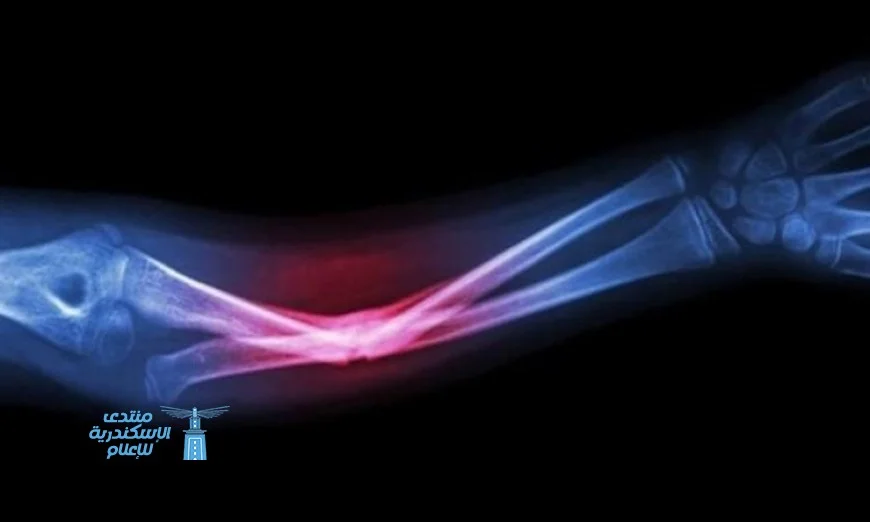

تشير الدراسات إلى أن هذه المادة الحيوية تتداخل بأمان مع جسم المريض، مما يساعد في تحفيز العمليات الشفائية الطبيعية ويشكل قاعدة لنمو عظام جديدة. إن هذا الابتكار قد يُعزز فعالية العلاجات المستخدمة في طب الأسنان وجراحة الوجه والفكين، إضافة إلى معالجة الإصابات العظمية.